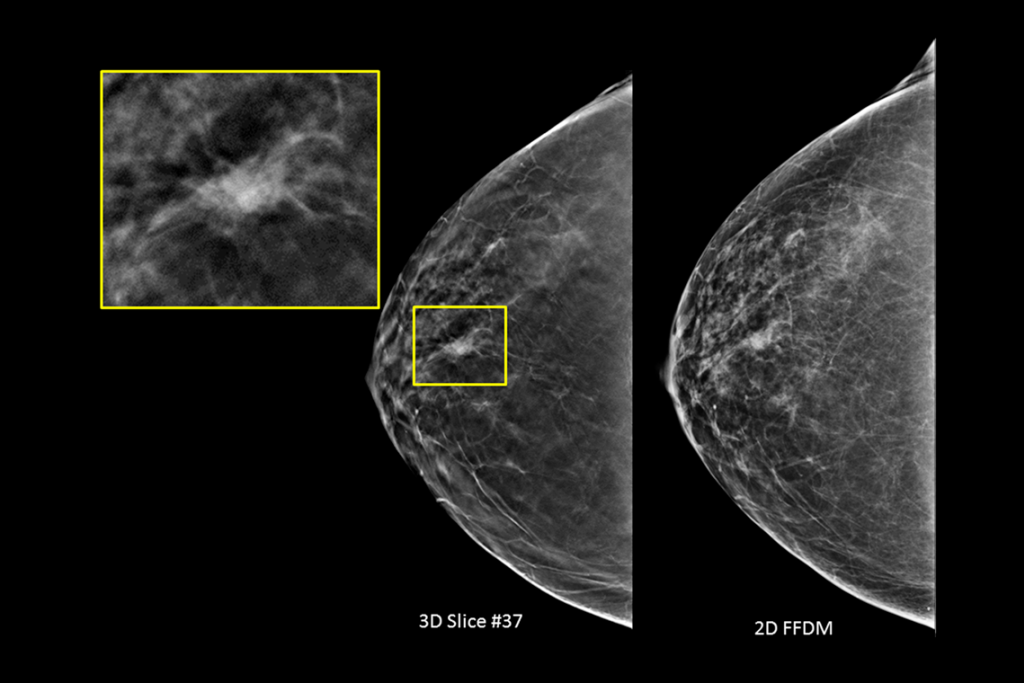

疑わしい病変が見られる乳房検査の臨床画像